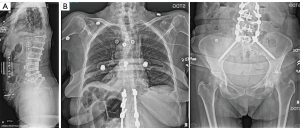

This was an 80-year-old woman with a past medical history of fibromyalgia, hepatic cirrhosis, de Quervain tenosynovitis, Ehlers-Danlos syndrome who initially presented for low back and bilateral lower extremity pain, specifically left thigh (anterior and posterior) and right gluteal pain. Preoperative imaging was notable for progressive degenerative scoliosis with widespread spondylitic changes producing areas of focal stenosis, L2–S1. She underwent left L2 and L3 transforaminal epidural steroid injection and right L5 transforaminal steroid injection with 100% diagnostic relief of lower extremity pain and was determined to be an appropriate candidate for staged L3–S1 anterior lumbar interbody fusion and T10-pelvis posterior spinal decompression fusion (Figure 1).

The patient underwent the anterior stage of her procedure without complication. The posterior annulus nor the posterior longitudinal ligament (PLL) were removed. The patient was extubated without complication and transferred to the postoperative care unit, where she was reporting some continuation of her right posterior leg pain, as well as some left anterior thigh numbness. The following day, she underwent her planned second stage T10-pelvis posterior spinal decompression fusion with O-arm navigated instrumentation. Standard open posterior approach was utilized. All screws were stimulated to indicate appropriate positioning and there was no evidence by any means for pedicle wall violation. Following this, open decompression was performed, including: partial decompressive laminectomy at L2, L3, L4, and L5 with total decompressive facetectomy at left L2/3, left L3/4, right L4/5. Bone morphogenetic protein (BMP), local autograft, as well as crushed cancellous allograft and submicron topography biphasic calcium phosphate granules were utilized to promote fusion. Rods were placed and final tightening was performed with appropriate positioning of implants. Final Valsalva to 40 mmHg was negative for any evidence of CSF leak and there were no complications noted intraoperatively (Figure 2). Two deep subfascial drains were placed in the area of the decompression and held to suction, with appropriate serosanguinous drainage.

The remainder of the patient’s hospital course was uncomplicated and prior to discharge standing films were obtained and were unremarkable (Figure 4). Patient was discharged to the inpatient rehabilitation unit and she demonstrated improved mental status and full motor and sensory function in bilateral upper and lower extremities with only some mild residual left thigh altered sensation similar to her preoperative baseline. She was admitted to the inpatient rehabilitation unit for 1 week prior to eventual discharge home.

A 71-year-old man with a past medical history of hypertrophic obstructive cardiomyopathy (prior septal myomectomy 2018), chronic obstructive pulmonary disease (COPD), hypertension, gastroesophageal reflex disease with Barrett’s esophagus, hyperlipidemia presented for low back pain with neurogenic claudication and radicular symptoms. Preoperative imaging demonstrated grade 1 spondylolisthesis at L4/5 and right greater than left L4/5 lateral recess stenosis and L4 foraminal stenosis. He was considered an appropriate candidate for L4/5 Total Posterior Spinal System (TOPS) (Figure 5).

The patient underwent uncomplicated scheduled L4/5 TOPS procedure. Following exposure, instrumentation was performed with placement of 7.5- and 6.5-mm pedicle screws at L4 and L5 with use of navigation. Total facetectomy was performed bilaterally at L4/5 as well as posterior column osteotomy at L4 and L5, as well as partial laminectomy L3 and L5 up to insertion of the ligamentum flavum and completed central decompressive laminectomy at L4. The TOPS device is rather large, and therefore a complete L4 and typically partial L3 laminectomy is needed, resulting in a generous multi-level decompression in the area of maximal stenosis. Following decompression, Valsalva to 40 mmHg was performed without evidence of CSF leak. Finally, a 21-mm large footprint TOPS device was placed with confirmation of appropriate positioning on intraoperative fluoroscopy. A subfascial drain was placed to bulb suction.